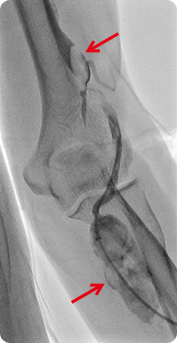

(диализ)- ① Гемодиализ

поликистозной болезни почек, гломерулонефрита, старости, ожирения и гиперлипидемии в течение более 3 месяцев, то диагностируется хроническое заболевание почек (хроническая почечная недостаточность). Если состояние ухудшается и почка становится полностью дисфункциональной, то это считается конечной стадией почечной недостаточности, и наиболее распространенной практикой в этом случае является гемодиализ. Часть крови забирается в аппарат для диализа, где из нее отфильтровываются отходы, а затем кровь возвращается обратно в организм. Проводится примерно 3 раза (по 4 часа каждый сеанс) в неделю.